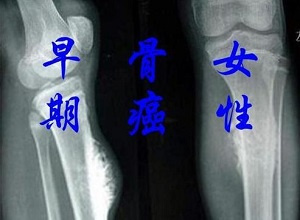

郑州看骨肿瘤中医馆哪家好?骨癌是一种非常可怕的疾病,所以即使是早期也应该引起我们的注意,以避免出现不可逆转的事情。那么,你知道骨癌的早期症状吗?下面一起来了解一下!